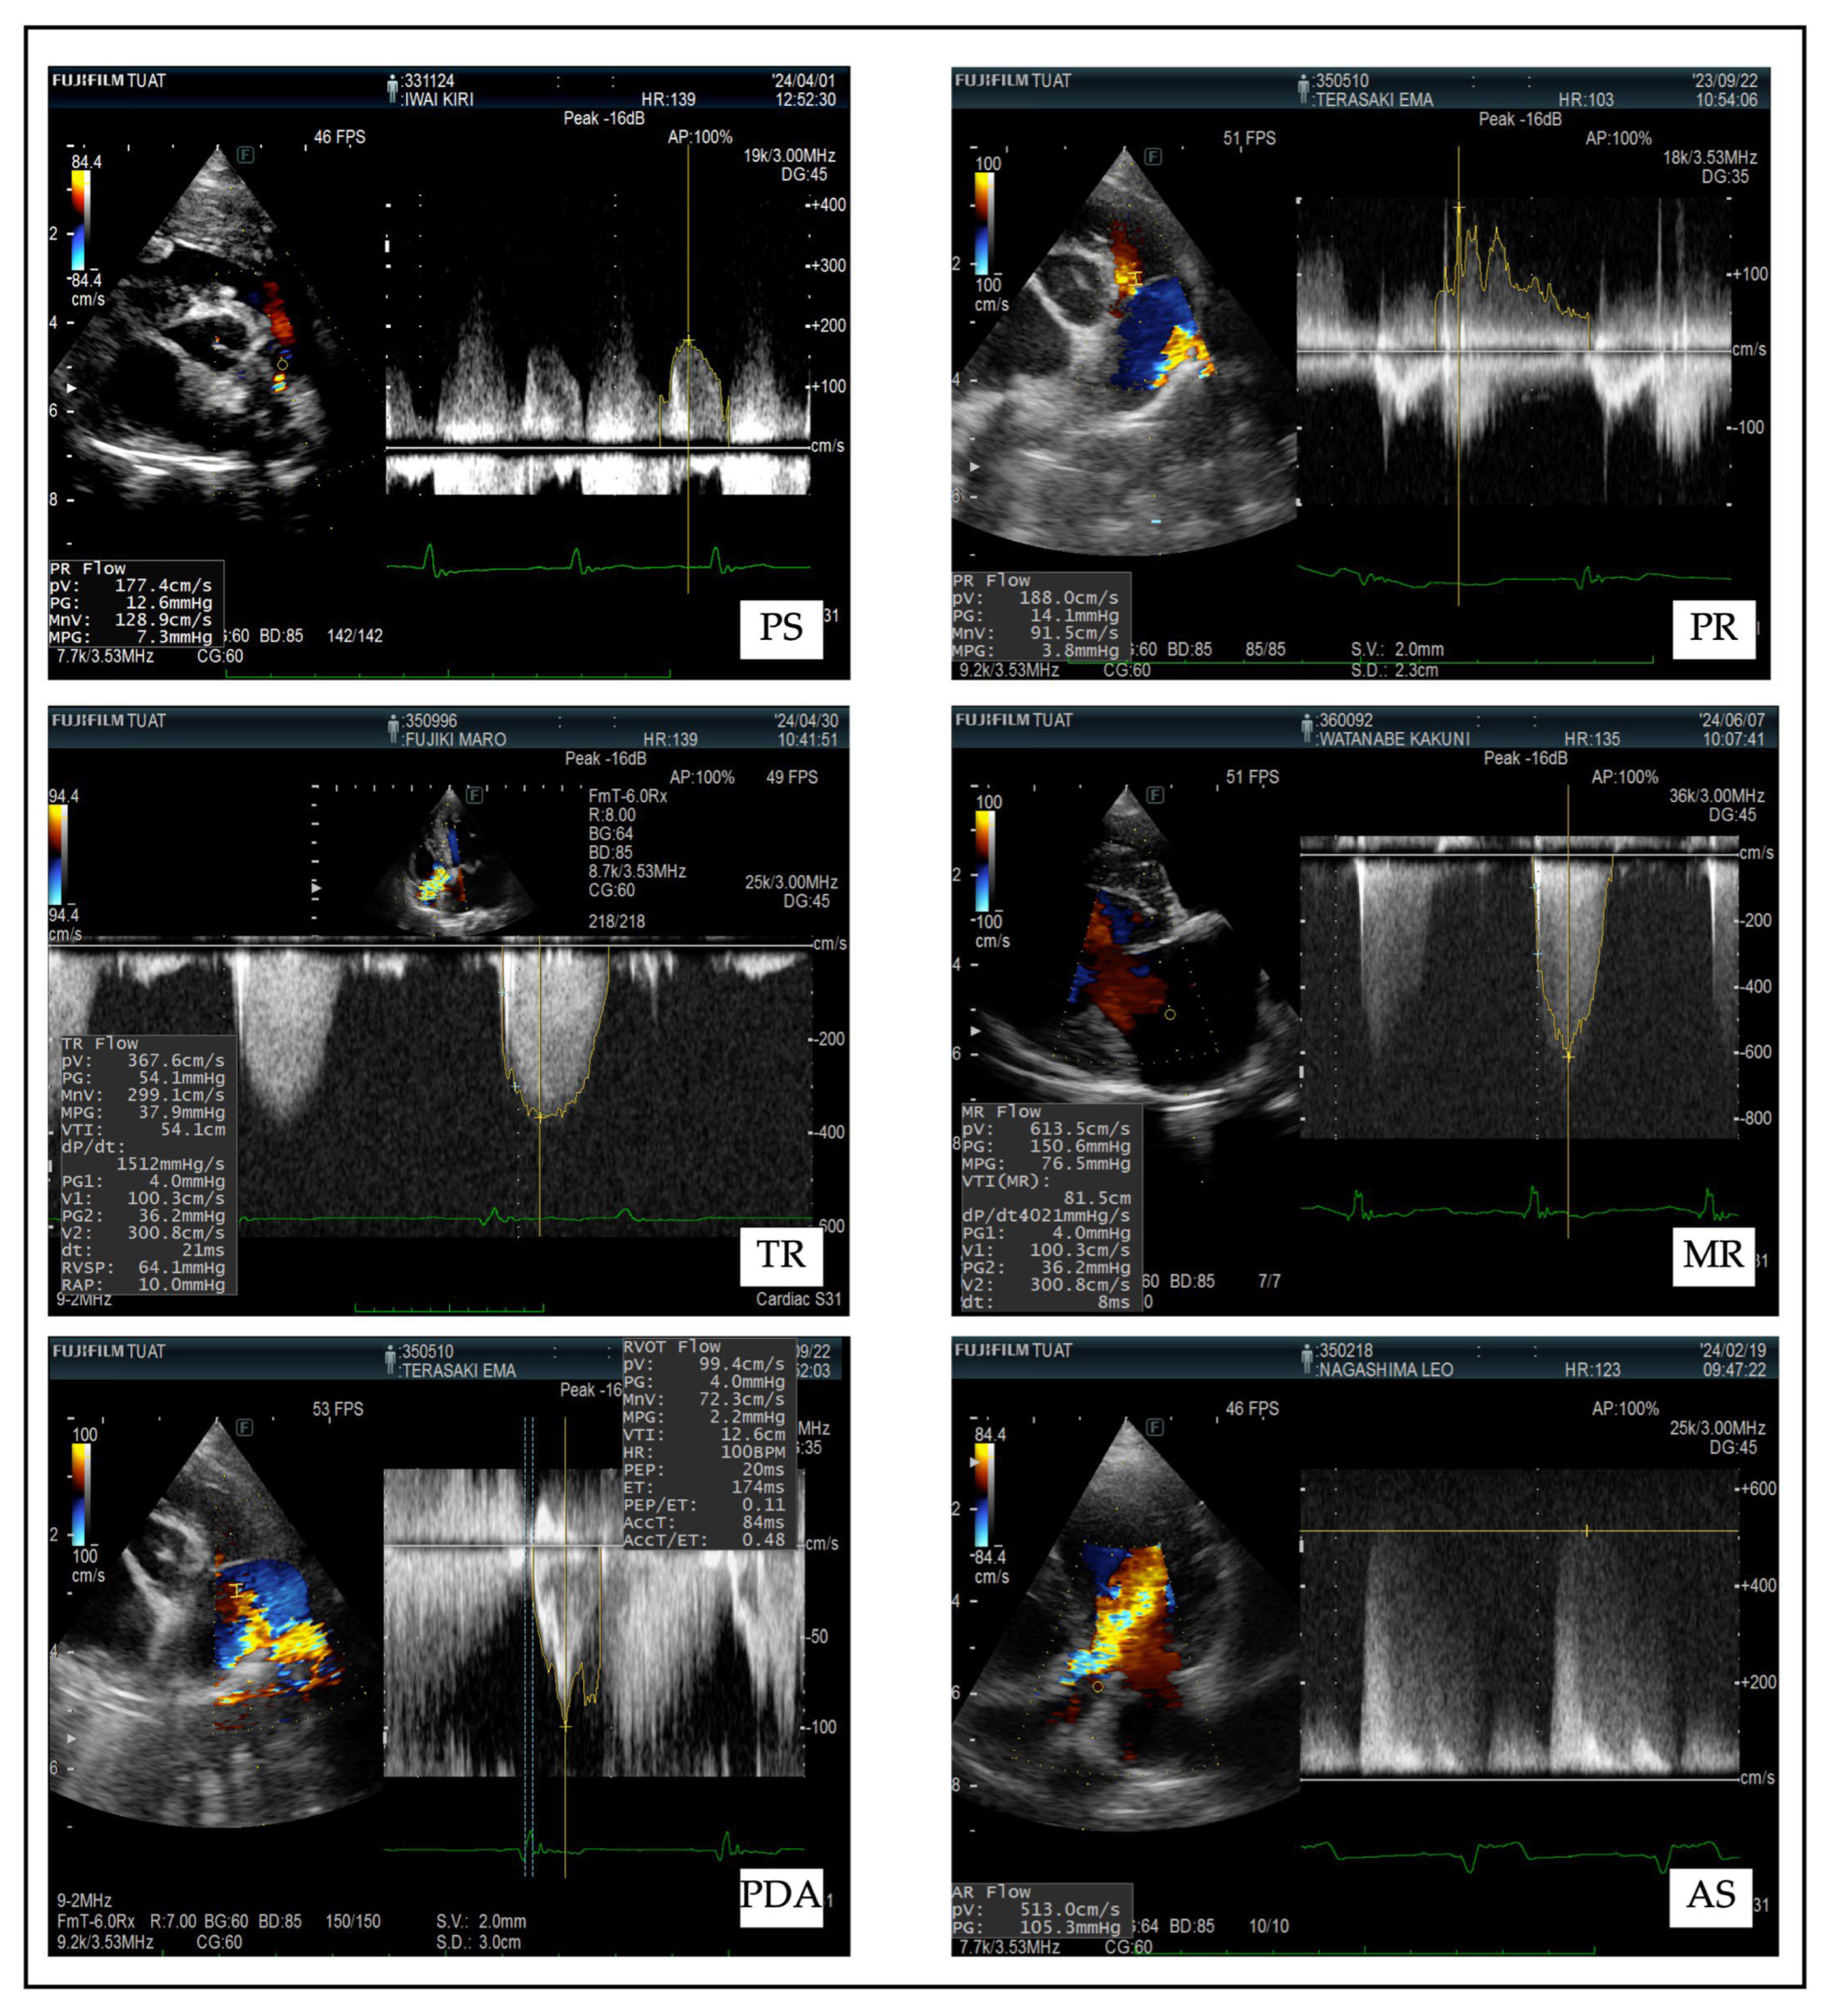

| Disease | Diagnostic Features | Doppler Parameters | Clinical Signs |

|---|---|---|---|

| Pulmonary Stenosis (PS) |

|

| Pulmonary Regurgitation (PR) |

| Tricuspid Regurgitation (TR) |

| Mitral Regurgitation (MR) |

| Aortic Stenosis (AS) |

| Patent Ductus Arteriosus (PDA) |